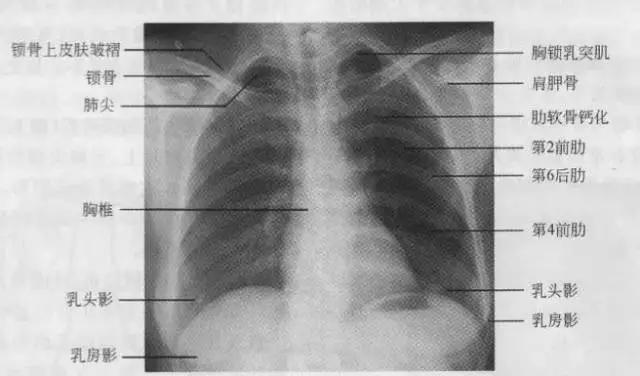

1、胸部正位片

临床拍标准的胸部正位片其实是后前位片,如上图

正常胸部后前位片

7、胸廓

正常胸廓由软组织与骨骼组成,两侧对称。

① 骨性结构: 肋骨、锁骨、肩胛骨、胸椎

② 软组织结构:胸锁乳头肌、锁骨上皮肤皱褶、胸大肌、女性乳房 / 乳头